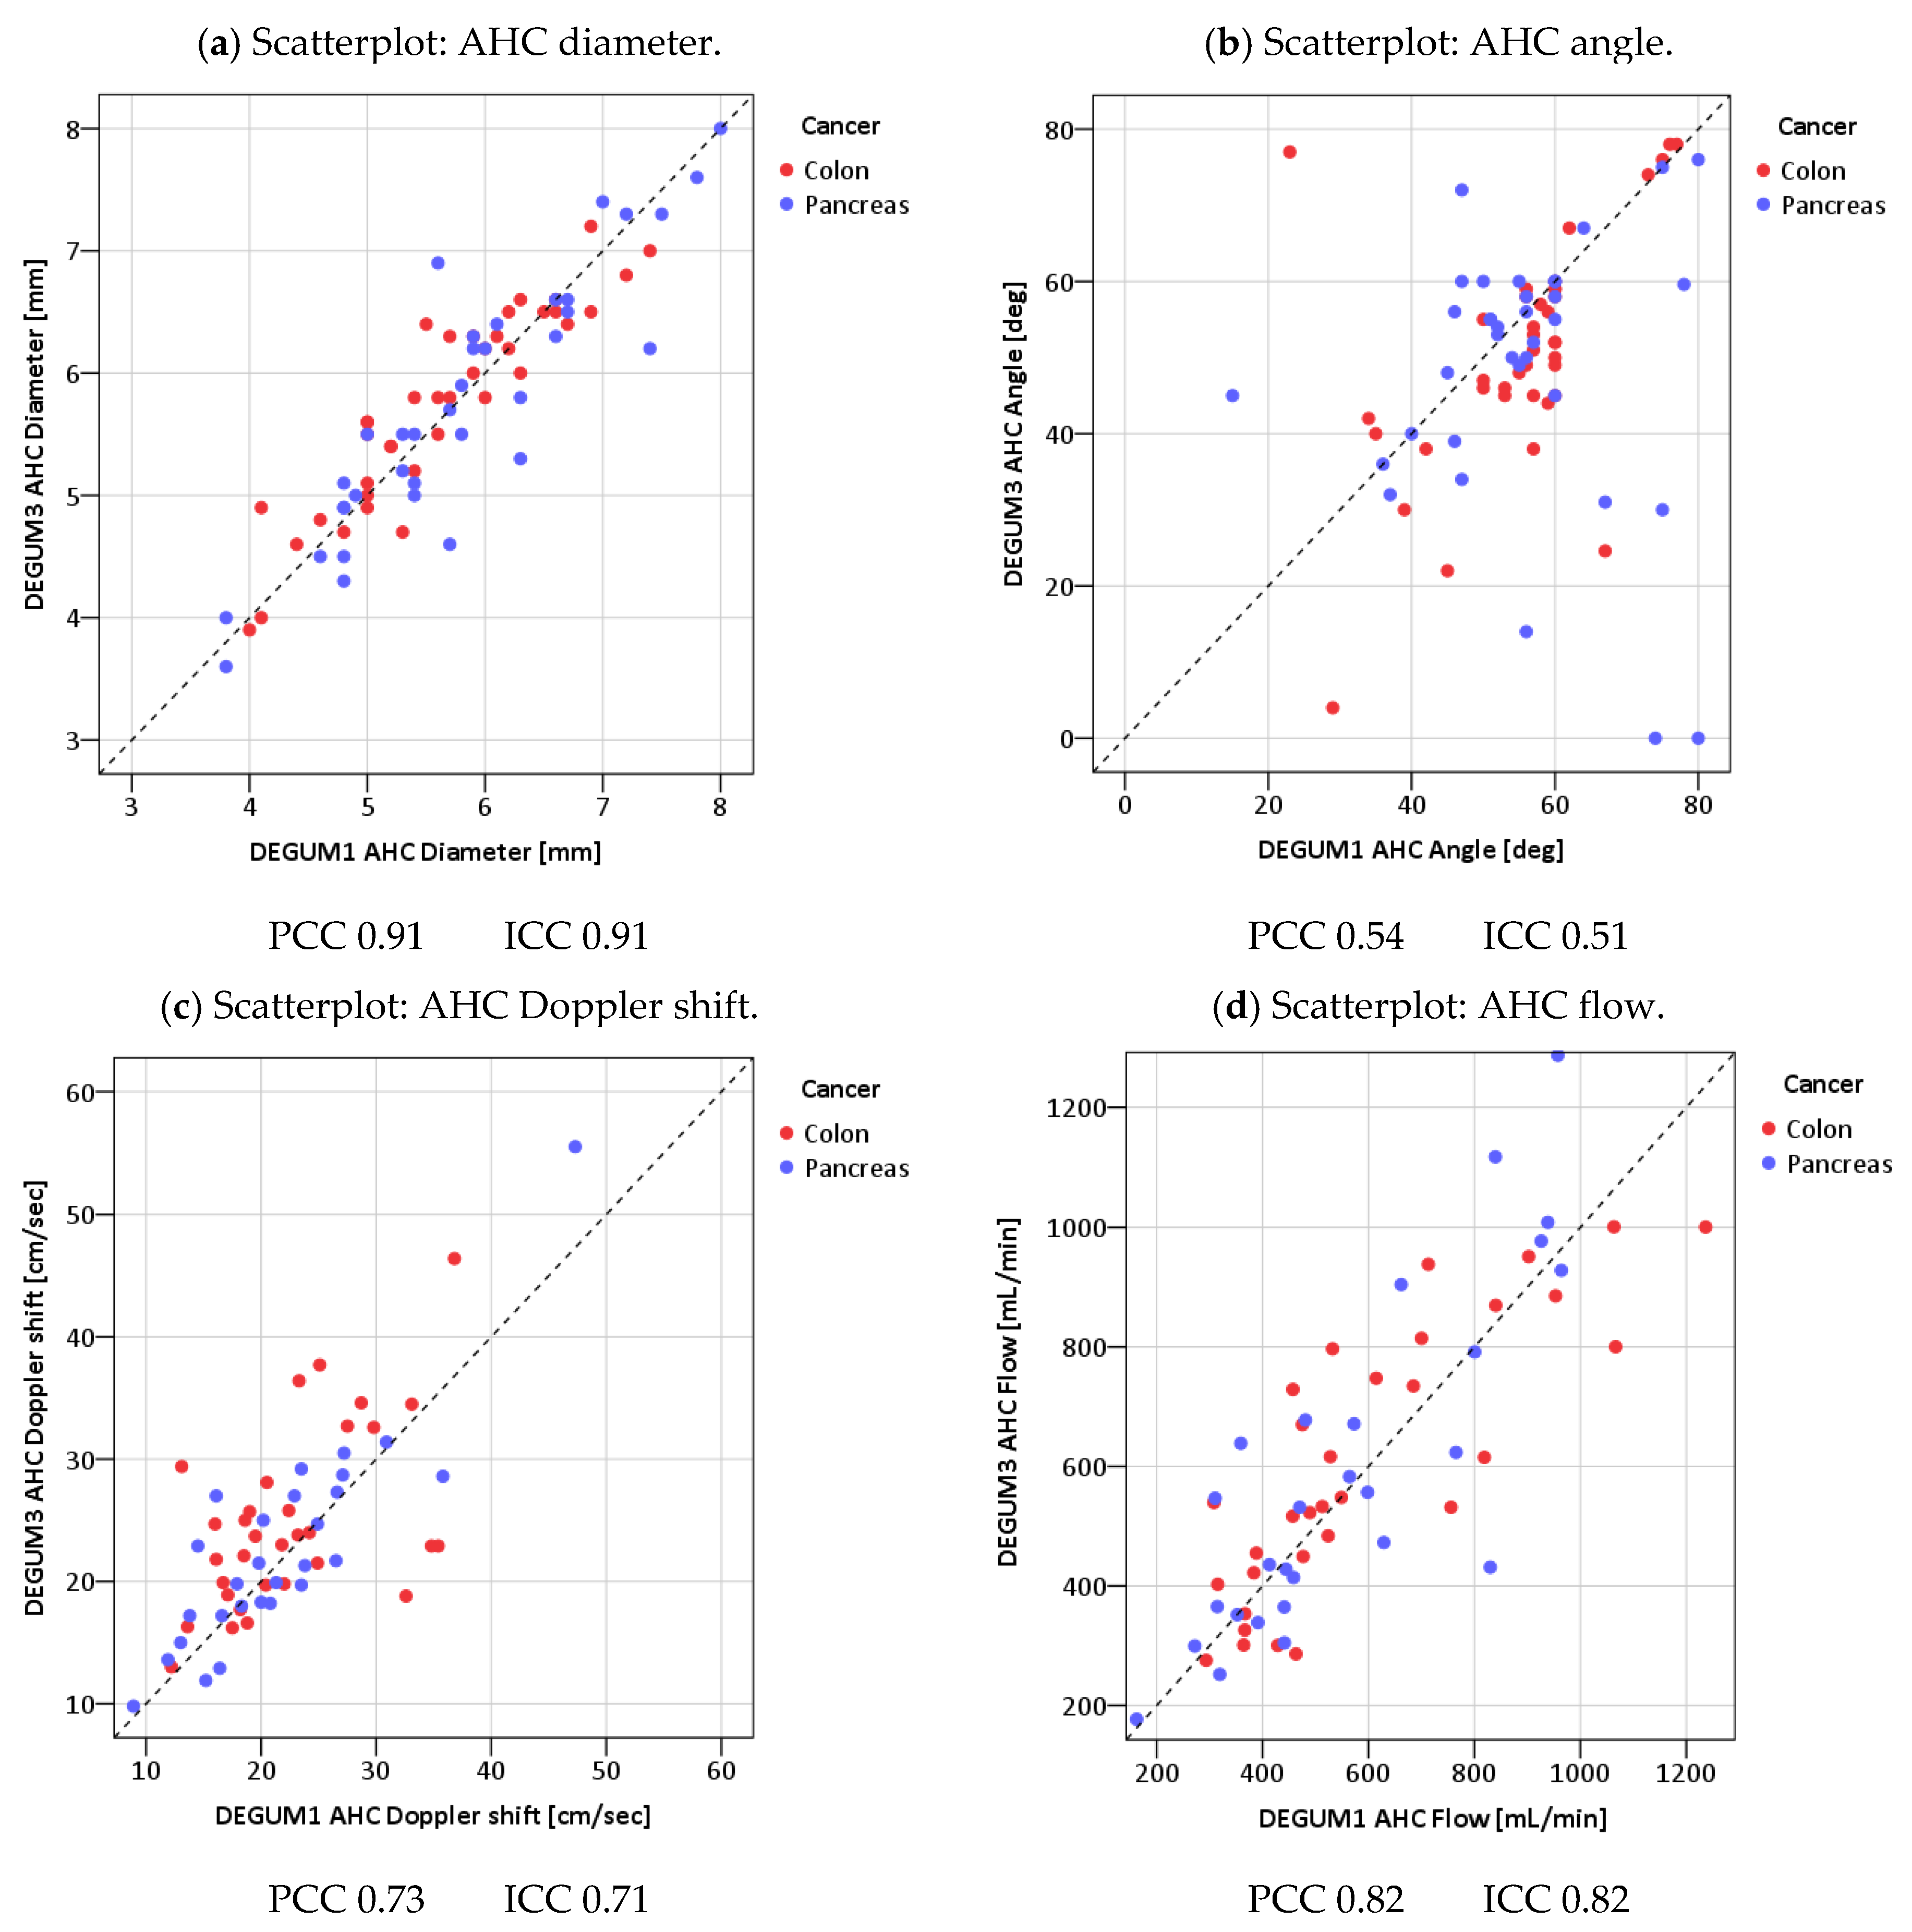

3.2. Measured Values and Calculated Blood Flow

| Parameter | Diameter [mm] | Insonation Angle | Doppler Shift [cm/s] | Flow [mL/min] |

|---|---|---|---|---|

| N | 79 | 79 | 79 | 79 |

| Mean D1 (SD) | 10.3 (1.3) | 31.7 (16.2) | 11.5 (2.7) | 712 (236) |

| Mean D3 (SD) | 10.1 (1.4) | 34.0 (14.9) | 11.9 (2.3) | 729 (238) |

| Mean tot (SD) | 10.2 (1.3) | 32.8 (15.5) | 11.7 (2.7) | 720 (237) |

| Mean Diff (SD) | −0.15 (0.74) | 2.4 (14.8) | 0.4 (2.5) | 17 (160) |

| p(Bias) | 0.20 | 0.26 | 0.11 | 0.55 |

| p(Var) | 0.57 | 0.29 | 0.81 | 0.82 |

| PCC | 0.85 | 0.55 | 0.57 | 0.77 |

| ICC (95% CI) | 0.84 (0.77; 0.90) | 0.54 (0.37; 0.68) | 0.56 (0.39; 0.70) | 0.77 (0.67; 0.85) |

| MVC | 0.04 | 0.33 | 0.12 | 0.11 |

| B/A Limits | (−1.6; 1.3) | (−26.7; 31.4) | (−4.5; 5.3) | (−297; 331) |